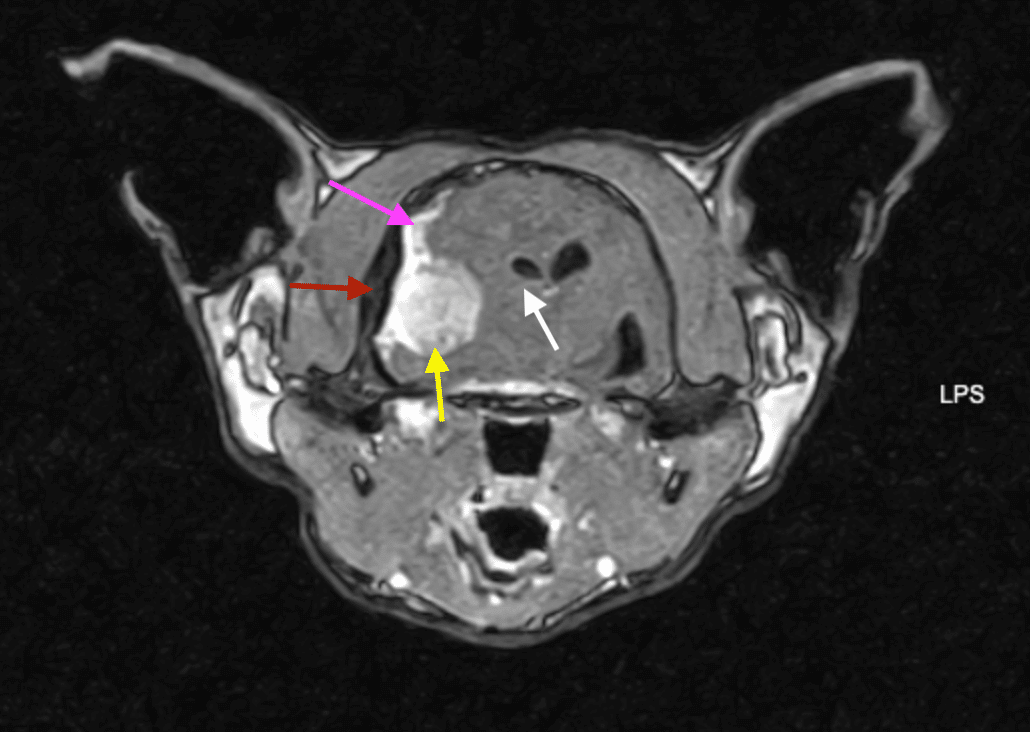

Immagine patognomonica di Risoananza Magnetica di encefalo di gatto. Sequenza  trasversa T1 pesata dopo mezzo di contrasto che evidenzia neoformazione ( meningioma) freccia gialla, effetto massa freccia bianca, dural tail freccia rosa e ispessimento calvario freccia rossa.

La Risonanza Magnetica (RM) dell’encefalo resta il gold standard per l’esame d’elezione per la diagnosi presuntiva. Il meningioma si presenta tipicamente come una massa extra-assiale ben definita, con intensa e omogenea presa di contrasto e caratteristico “dural tail sign”. La RM ha un’accuratezza diagnostica del 70% nel cane e dell’82% nel gatto.